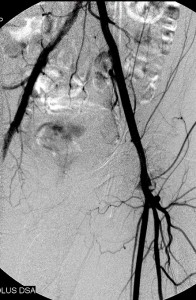

The images below illustrate percutaneous stenting of stenosis of the distal proximal and the mid left common iliac artery, without disease of the left external iliac artery in one of my patients who presented with left calf claudication. CTA of his abdominal aorta and arterial duplex ultrasound of his lower limbs ( images not shown) revealed left iliac stenosis, confirmed by the digital subtraction angiographic images in the first row. He did well following stenting of the diseased artery. Iliac arterial stenting stays open for nearly as long as surgical revascularization and at much less the morbidity and cost of the latter.